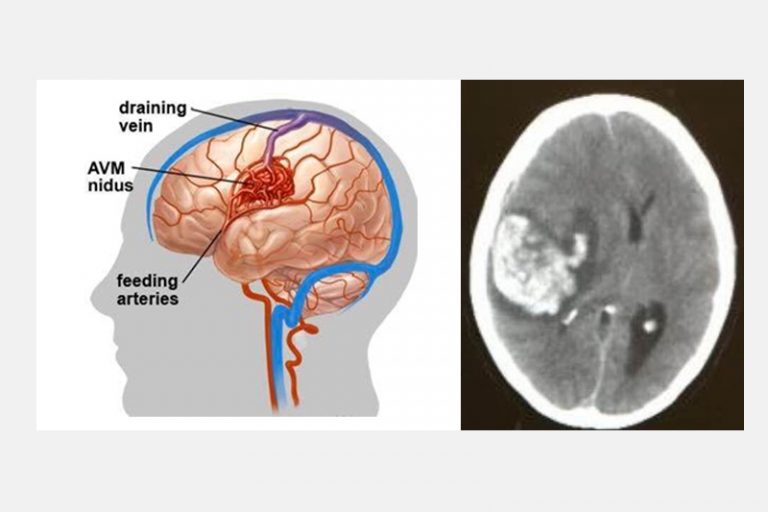

四歲小朋友,出生以來一切健康正常,沒有任何症狀,有一天隨著母親逛街,突然感到頭部劇痛,然後急速昏迷。送到醫院證實是先天性大腦動靜脈畸形血管瘤爆破而引致的嚴重出血性中風,他雖然從死亡鬼門關好不容易才被拯救出來,但即使經過多年的救治,也不能逆轉中風對大腦神經的永久損害,如今小孩仍然患有嚴重殘疾,不能與人溝通及需要長期臥床。

先天性大腦動靜脈畸形血管瘤爆破而引致的嚴重出血性中風

兩位分別是16歲的少年和56歲的男士,在沒有任何徵象之下做了詳盡的身體檢查,三維立體腦血管造影顯示兩人的大腦都有先天性的腦血管動靜脈畸形,在專科醫生建議之下透過了一段時間的觀察和保守治療,其後利用了微創內血管治療加上放射治療,畸形血管得到了有效的根治,病人與生俱來的大腦炸彈得到了拆除,減低了他們將來出血性中風的可能性。

三維立體腦血管造影顯示左邊大腦都有先天性的腦血管動靜脈畸